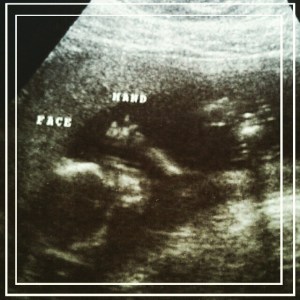

Best moment of this week: Having our 18 week appointment & hearing our little man’s heartbeat (steady & strong at 154 🙂 )

Gender: Boy!!